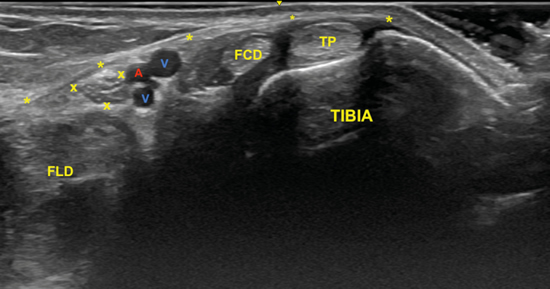

El nervio tibial, que se sitúa en superficie a las estructuras musculotendinosas y bajo la fascia crural, de forma habitual está dispuesto posterior a los vasos tibiales posteriores (Figura 6).

Figura 6. Túnel tibiocalcáneo. El examen en eje corto, bajo la fascia crural (*) y de anterior a posterior, muestra el tendón tibial posterior (TP), el tendón flexor largo de los dedos (FCD) aún con fibras musculares, y el músculo flexor largo del primer dedo (FLD). Entre estas dos estructuras se encuentra el haz neurovascular que está formado por las venas (V), la arteria (A) tibial posterior y por el nervio tibial (rodeado por X).

El examen para localizar la división del nervio tibial continúa desplazando la sonda en eje transverso y en sentido cráneo caudal desde la posición anterior (Figura 4) en busca del túnel del tarso distal o túnel talocalcáneo (Figura 10), donde el nervio se divide en el nervio plantar medial y nervio plantar lateral (Figura 11), 1.3 a 2.5 cm proximal a la división de la arteria tibial posterior3,9. Dellon-Mackinnon describieron la división del nervio tibial en relación al eje entre el centro del maléolo medial y la tuberosidad del calcáneo (línea Dellon-Mackinnon) (Figura 12) en un 90 % de los casos (55 % en la línea, 16 % 1 cm distal y 19 % 1 cm proximal)10. Más tarde, Moroni y cols. refieren tal división 16.4 mm proximal a dicho eje8.

Figura 11. Imagen sonográfica de la diferenciación del nervio plantar medial (M) y del nervio plantar lateral (L) debajo de la arteria y venas (A, V) y sobre el tendón flexor largo del primer dedo (FLD). En superficie el retináculo flexor (*).

La imagen sonográfica se centrará en el espacio situado bajo la fascia profunda del músculo abductor del primer dedo, por donde discurrirán los haces neurovasculares plantar medial y plantar lateral, diferenciados y separados por el septo de Heimkes o interfascicular3. El nervio plantar medial se muestra con mayor sección que el nervio plantar lateral, y las venas laterales con mayor luz que las mediales (Figura 14).